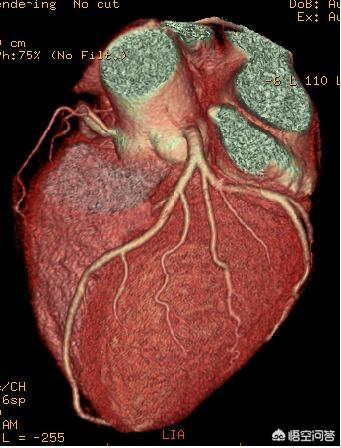

3. l'angiographie coronarienne : elle consiste à introduire une aiguille à demeure dans le bras, puis à injecter un produit de contraste et à réaliser un scanner des vaisseaux sanguins du cœur comme on le fait pour un scanner des poumons. La sensibilité et la spécificité de l'angiographie coronaire pour le diagnostic de sténose luminale sont respectivement de 87,5 % et 97,2 %, et la valeur prédictive positive et la valeur prédictive négative sont respectivement de 82,4 % et 98,1 %. L'angiographie coronaire peut être réalisée en ambulatoire. Il s'agit d'un examen non invasif, adapté aux patients qui ne souhaitent pas subir une coronarographie.

Par exemple, la maladie coronarienne la plus courante est le diagnostic clair de la maladie coronarienne, à l'heure actuelle, le renforcement de l'artère coronaire principale par la tomodensitométrie et l'angiographie de l'artère coronaire, en plus de l'électrocardiogramme, du test de charge d'exercice et de la scintigraphie nucléaire cardiaque et d'autres tests, qui peuvent aider à déterminer l'ischémie myocardique. En fait, la norme la plus couramment utilisée et la plus fiable reste la coronarographie, mais dans le pays, l'examen nécessite généralement une hospitalisation et le coût est plus élevé.

En outre, si vous souhaitez observer l'état des vaisseaux sanguins du cœur, vous pouvez d'abord procéder à une angiographie coronarienne afin de déterminer si les vaisseaux sanguins sont calcifiés ou rétrécis, ainsi que le degré et l'emplacement du rétrécissement. Toutefois, il ne s'agit là que d'un examen préliminaire. Pour refléter avec précision l'état des vaisseaux sanguins, une coronarographie est également nécessaire ; une fois les problèmes détectés par cet examen, la pose d'une endoprothèse et d'autres traitements peuvent être effectués en temps utile.

Chez un patient atteint d'une maladie coronarienne, un électrocardiogramme bien établi, un électrocardiogramme ambulatoire et une épreuve d'effort sont nécessaires pour déterminer indirectement l'ischémie myocardique. L'échographie cardiaque 2D permet de déterminer s'il existe une ischémie myocardique en fonction du mouvement de la paroi ventriculaire. La scintigraphie nucléaire du myocarde peut déterminer s'il y a une ischémie myocardique par la présence de défauts de remplissage et peut également déterminer la fonction cardiaque. L'angio-tomodensitométrie coronaire (CT angiography) et la coronarographie permettent de déterminer l'emplacement et l'étendue des sténoses et des calcifications. L'infarctus aigu du myocarde est également pris en compte pour améliorer les marqueurs de lésions myocardiques.

Sixièmement, la tomodensitométrie à plusieurs rangs. La tomodensitométrie à plusieurs rangs est utile pour le dépistage des maladies coronariennes et des maladies vasculaires coronariennes.

CT coronaire

Le scanner coronaire est un examen auxiliaire utilisé pour vérifier si les artères coronaires sont normales. Tout d'abord, le système d'imagerie est responsable du balayage, et les données obtenues lors du balayage sont stockées et calculées par le système informatique, puis l'image est analysée et reconstruite, de sorte que les vaisseaux sanguins des artères coronaires sont visualisés devant le médecin, ce qui peut être utilisé pour diagnostiquer la maladie. Ce test est principalement utilisé pour aider au diagnostic de la sténose de l'artère coronaire, la précision du scanner coronaire n'est pas aussi bonne que l'imagerie, et le traitement informatique de l'image peut présenter des pseudo-différences, l'avantage est que le coût du scanner coronaire est relativement plus faible, moins traumatisant.